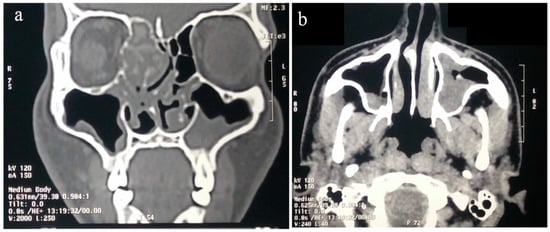

8.1. Imaging